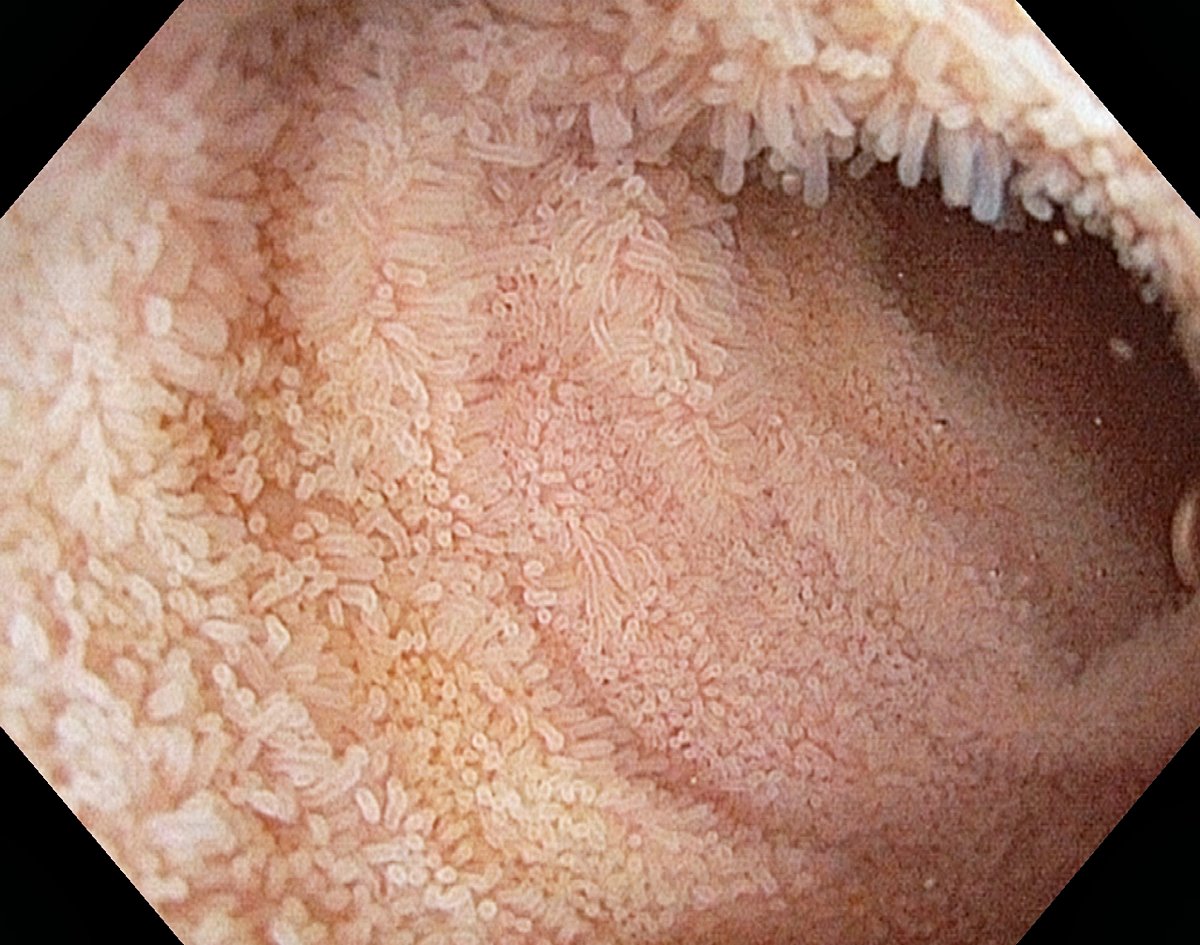

IMAGE: Normal villi in the terminal ileum

Normal villi in the terminal ileum